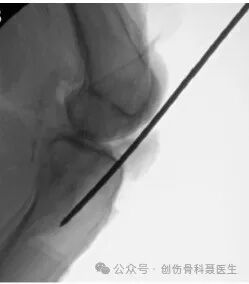

切口入点:正位位于胫骨机械轴与胫骨平台的交点,即胫骨外侧髁间棘的内侧缘,侧位位于胫骨平台与胫骨干移行区的分水岭上

标准的正位X片:正位X片的机械轴做一直线,在胫骨平台外侧缘做机械轴的平行线,该平行线在正位片上要平分腓骨头

标准的侧位X片,股骨内外侧髁基本重叠,内外侧胫骨平台基本重叠,侧位片上,进针点位于平台与胫骨干的分水岭